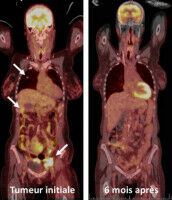

Santé - Pharmacologie - 10.02.2021

Une équipe de l'Université de Genève et des HUG est parvenue à sauver la vie d'une femme dont le cancer agressif lui laissait cinq mois d'espérance de vie. Ce «miracle» met en lumière l'importance des traitements fondés sur l'immunothérapie. La lutte contre le cancer ne se solde pas toujours par une victoire.